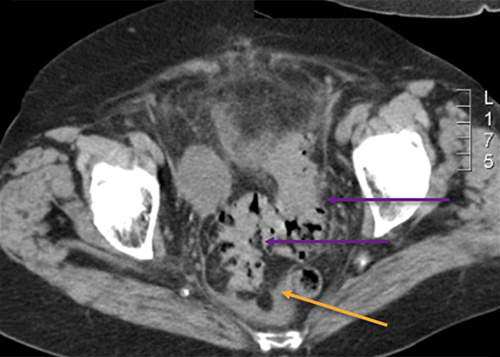

Le diagnostic est possible, il peut en effet donner des douleurs fébriles en fosse iliaque gauche, d’autant que le patient pratique des injections sous-cutanées d’insuline dans sa cuisse, ce qui peut être une porte d’entrée de l’infection.

Dans ses antécédents, on retient une appendicectomie dans l’enfance, une hypertension artérielle (HTA) traitée par bisoprolol et un diabète insulino-dépendant nécessitant des injections d’insuline sous-cutanées dans la cuisse.